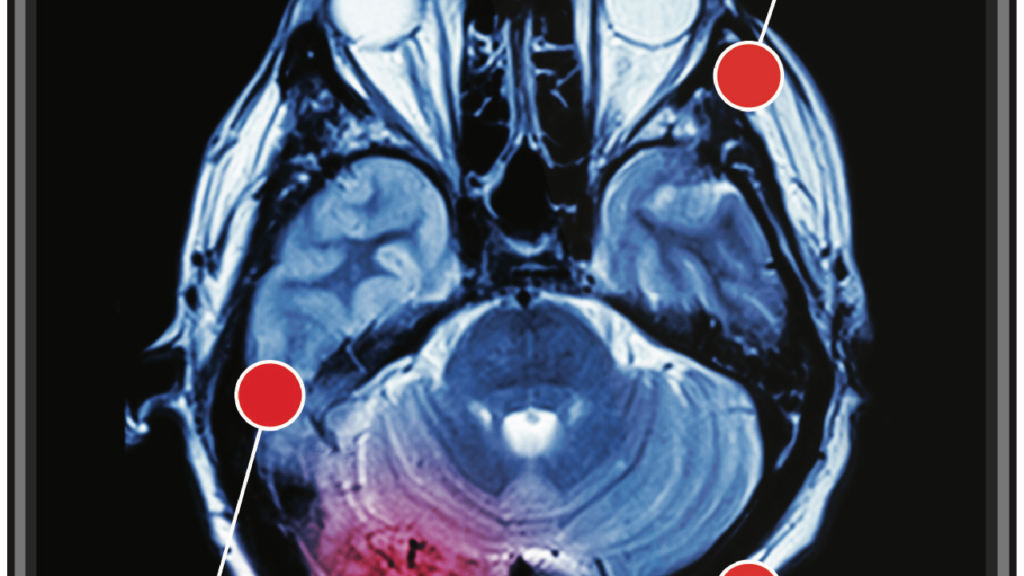

6. L’Université hébraïque (Jérusalem) a développé un neurostimulateur électrique (piles) qui est implanté dans la poitrine des patients atteints de la maladie de Parkinson, semblable au stimulateur cardiaque. Les émissions de cet appareil bloquent les signaux nerveux qui provoquent des tremblements.